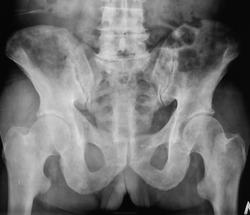

Пол пациента: Мужской пол Тип патологии: Другое Область исследования: Скелетно-мышечная система Методы исследования: Rg Пациент направлен на рентгенографию костей таза https://radiomed.ru/sites/default/files/styles/case_slider_image/public/user/12/2.dscn0421.jpg?itok=7FIwzRQD ID:23926 Wed, 24/10/2012 - 21:42 #1 И.Бондаренко Offline Last seen: 1 day 22 hours ago Joined: 13.09.2011 - 22:55 Posts: 9214 Очень похоже на мтс. Какой возраст пациента? Wed, 24/10/2012 - 21:44 #2 Катенёв Валенти... Offline Last seen: 7 years 5 months ago Joined: 22.03.2008 - 22:15 Posts: 54876 71 год. Wed, 24/10/2012 - 22:30 #3 Катенёв Валенти... Offline Last seen: 7 years 5 months ago Joined: 22.03.2008 - 22:15 Posts: 54876 Продолжение.Приложения: Wed, 24/10/2012 - 22:39 #4 tatyana Offline Last seen: 4 years 6 months ago Joined: 24.06.2009 - 08:33 Posts: 2090 Валентин Львович, а какая здесь цель линейной томографии? Что ищете? простату? "самоуверенность дилетантов - предмет зависти профессионалов" Wed, 24/10/2012 - 22:41 #5 Катенёв Валенти... Offline Last seen: 7 years 5 months ago Joined: 22.03.2008 - 22:15 Posts: 54876 Ищем метастазы. Из областного ООД прислали к нам. У них в ООД (мать бы их) все под вопросами, ничего не сделали и отправили в ЦРБ с целым перечнем. Они, там под вопросом клинически выставили опухоль мочевого пузыря. Wed, 24/10/2012 - 22:47 #6 Катенёв Валенти... Offline Last seen: 7 years 5 months ago Joined: 22.03.2008 - 22:15 Posts: 54876 Срезали еще позвоночник.Приложения: Wed, 24/10/2012 - 23:17 #7 tatyana Offline Last seen: 4 years 6 months ago Joined: 24.06.2009 - 08:33 Posts: 2090 Катенёв Валентин Львович wrote: Ищем метастазы. Из областного ООД прислали к нам. Чё-то не въеду, а чё их искать то? практически тотальное преимущественно остеобластическое поражение. В ООД нет желания слазить пальцем в попу? "самоуверенность дилетантов - предмет зависти профессионалов" Thu, 25/10/2012 - 15:48 #8 Катенёв Валенти... Offline Last seen: 7 years 5 months ago Joined: 22.03.2008 - 22:15 Posts: 54876 И.Бондаренко wrote: Очень похоже на мтс. Спасибо коллега за коммент. Thu, 25/10/2012 - 15:50 #9 Катенёв Валенти... Offline Last seen: 7 years 5 months ago Joined: 22.03.2008 - 22:15 Posts: 54876 tatyana wrote: Чё-то не въеду, а чё их искать то? практически тотальное преимущественно остеобластическое поражение. В ООД нет желания слазить пальцем в попу? Спасибо Татьяна Валентиновна! В "нашем" ООД желания нет, нет не только..., но и никуда.

Очень похоже на мтс. Какой возраст пациента?

71 год.

Ищем метастазы. Из областного ООД прислали к нам.

У них в ООД (мать бы их) все под вопросами, ничего не сделали и отправили в ЦРБ с целым перечнем. Они, там под вопросом клинически выставили опухоль мочевого пузыря.

Чё-то не въеду, а чё их искать то? практически тотальное преимущественно остеобластическое поражение. В ООД нет желания слазить пальцем в попу?